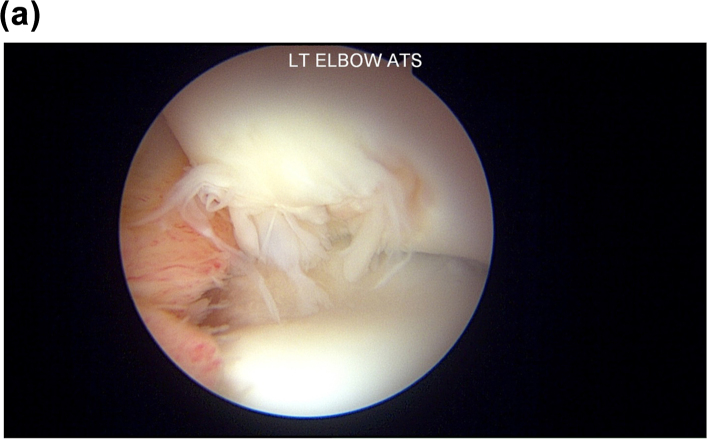

Fig. 5B.

Similar view to Fig. 5A with a 70-degree arthroscope from a posterior lateral portal showing the capitellum (above) after debridement and microfracture of the osteochondral lesion and resection of the plica.